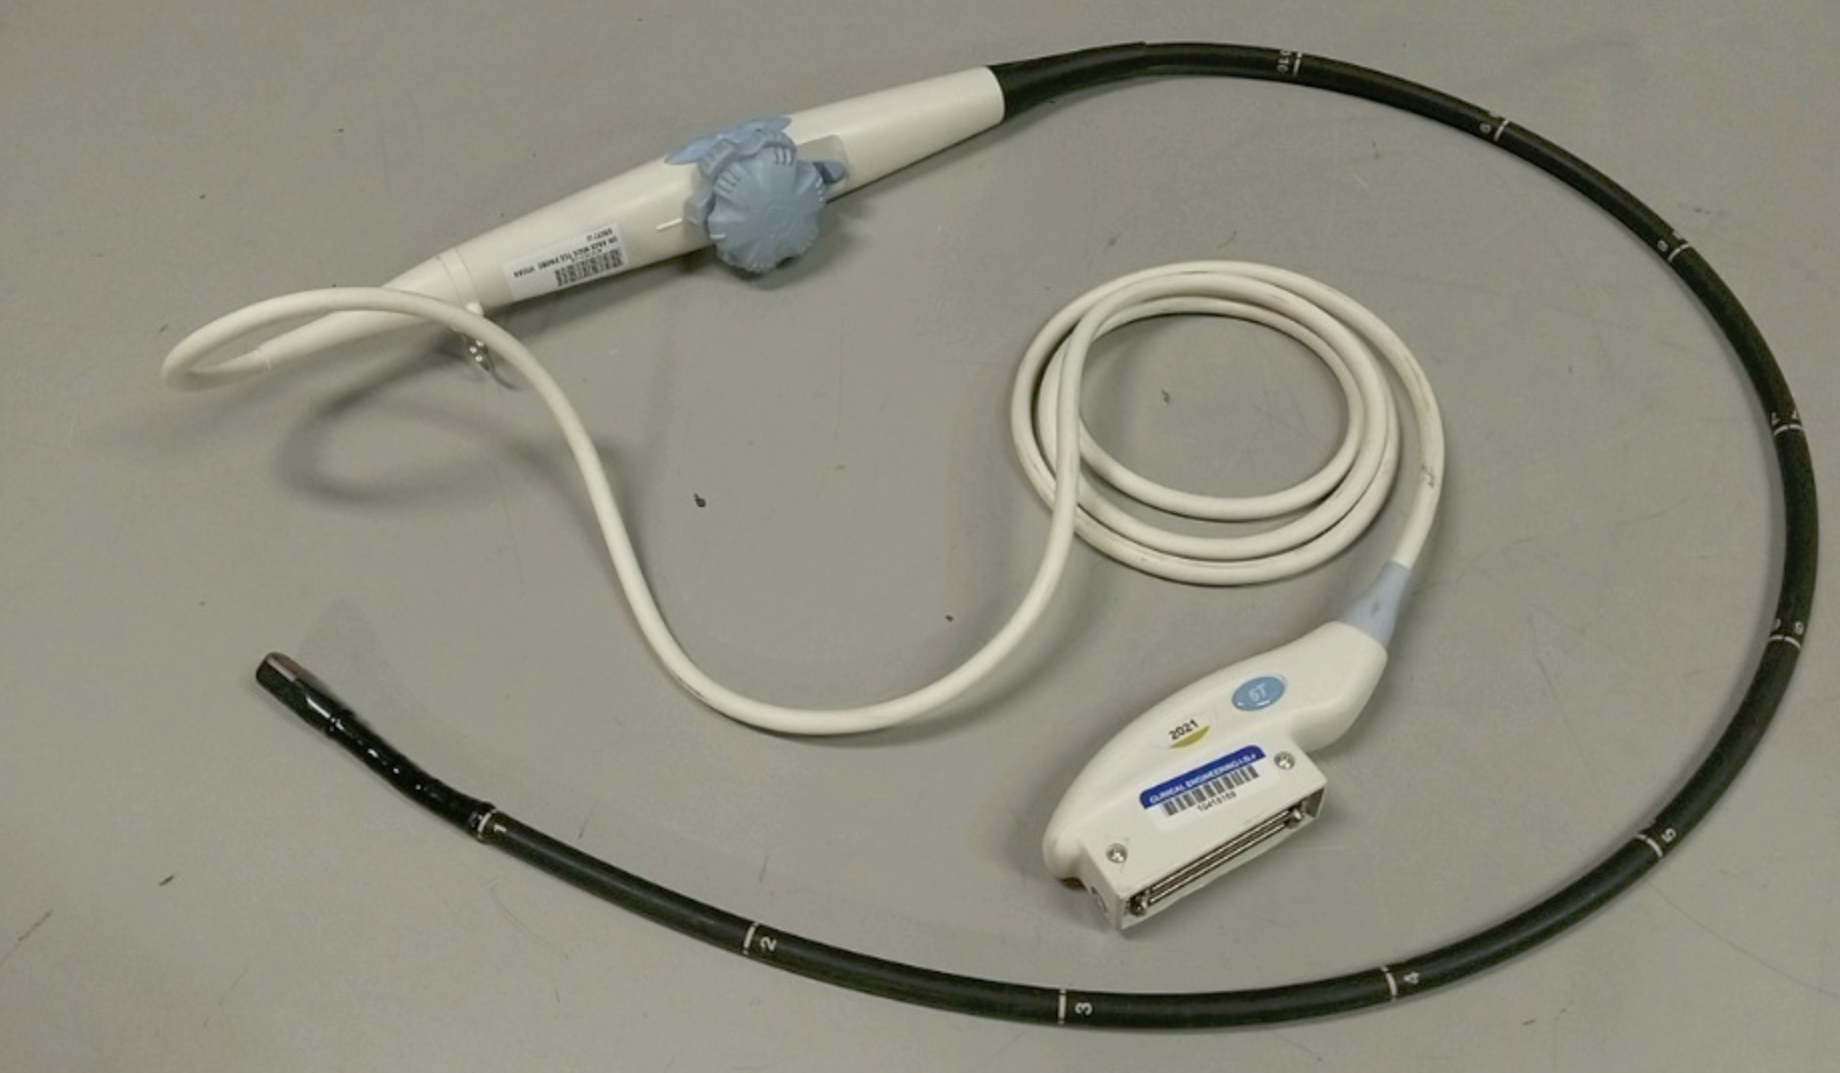

DIAGNOSTIC ULTRASOUND MACHINES FOR SALE